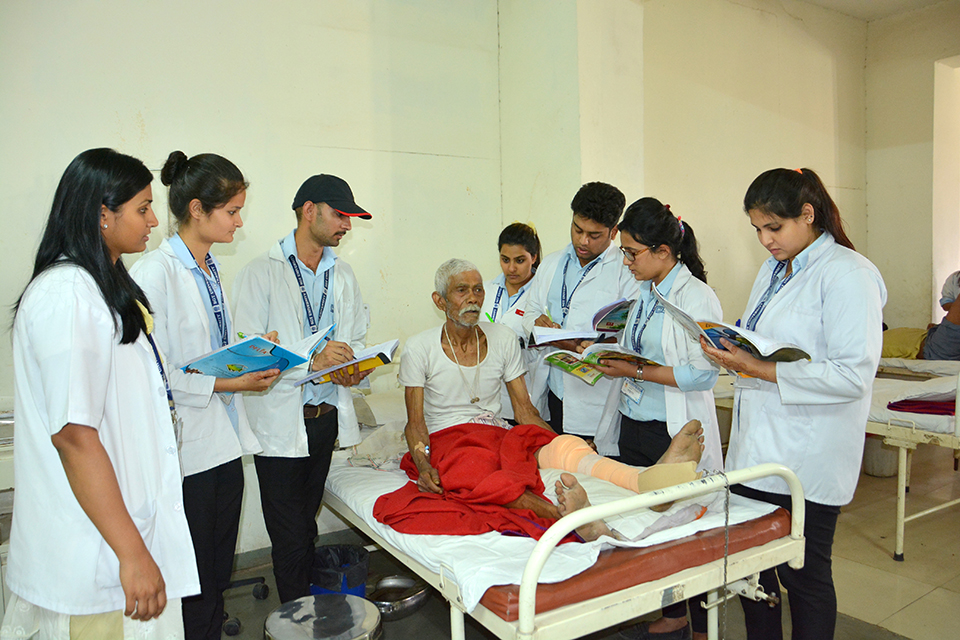

Our Team MEMBER

Experts Team

- Caring staff and nurses